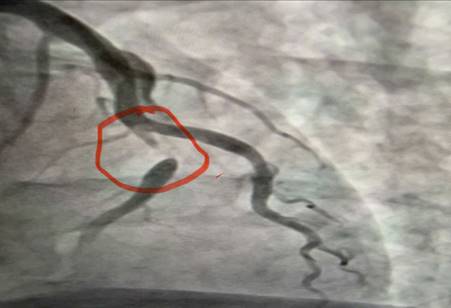

Hình ảnh nhồi máu cơ tim gây tắc 95% đoạn 1 động mạch liên thất trước

Ê-kíp bác sĩ khoa Nội tim mạch đã tiến hành chụp động mạch vành kết quả cho thấy: nhánh động mạch thủ phạm gây Nhồi máu cơ tim cấp là đoạn 1 động mạch liên thất trước hẹp 95%. Bệnh nhân đã được can thiệp nong và đặt Stent động mạch vành giúp tái thông dòng máu nuôi tim, hạn chế tối đa tổn thương cơ tim và các biến chứng nguy hiểm. Sau can thiệp mạch vành tái thông tốt, tình trạng người bệnh ổn định, các triệu chứng đau ngực giảm rõ rệt và tiếp tục được theo dõi, điều trị theo phác đồ chuyên môn.